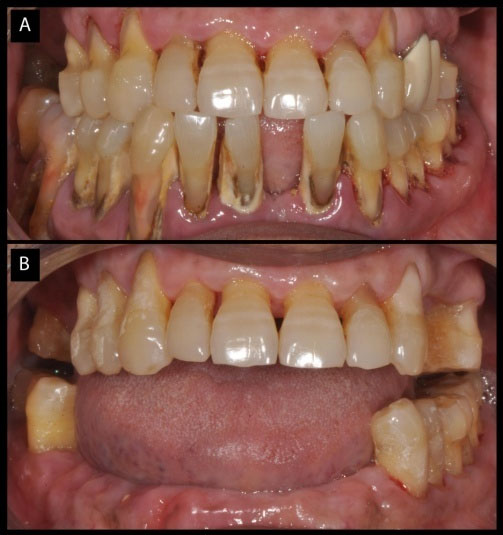

A completely edentulous patient

A 65-year-old female patient presented, complaining of inability to chew properly. Although the patient was in good health without any medication, oral neglect was unaccountable. On oral clinical examination, the entire dentition seemed mobile. There was >50% attachment loss on all the teeth, with grade 3 furcation involvement in lower molars bilaterally. Complete extraction was advised, except for teeth #25 and #35 to preserve the vertical dimension of occlusion (Figure 5, a, b and c). Complete dentures were fabricated after a tissue healing period of 6 weeks. The patient was kept on 3-month follow-ups to monitor oral hygiene maintenance.

japid-11-39-g005

Figure 5. (a) Chronic periodontitis patient; (b) 3D view showing the extent of bone loss; (c) Edentulism after extraction except for premolars to maintain the vertical height.